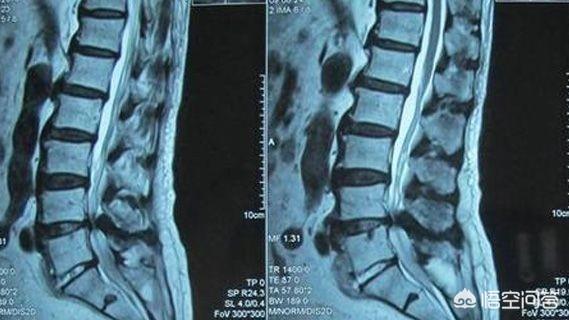

恶化这个词,用在椎间盘突出症上,不是很恰当啊,没那么可怕,一般来讲,如果腰椎间盘突出造成腰痛,相对较轻,如果造成腿痛和腿麻,表示神经根受压,会重一点,不过也不是麻木一定疼于疼痛,只是两种不同症状表现!

2.当一个人腰痛,逐渐的变成腰腿疼,则表示由单纯的硬膜囊受压,导致神经根受压,也表示症状在加重!

最多见的例如,L4-5椎间盘突出症,造成臀部外侧和腿外侧疼痛麻木,可以诱发臀中肌综合征,进一步加重臀部和腿外侧痛!

L5-s1椎间盘突出症,造成臀部后侧疼痛,造成梨状肌紧张,压迫刺激坐骨神经,诱发臀部和腿后侧疼痛,和椎间盘突出症混合!